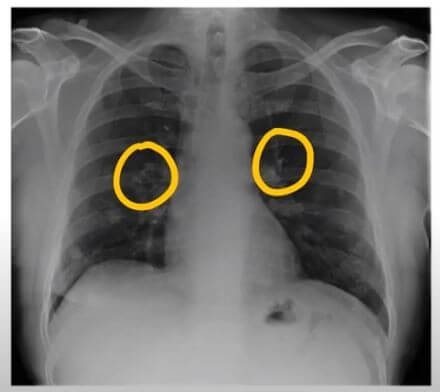

폐암의 초기증상은?

폐암은 초기에는 증상이 나타나지 않기 때문에 진단하기 어려운 암입니다. 그러나 폐암이 진행됨에 따라 다음과 같은 증상이 나타날 수 있습니다.

- 기침: 폐암의 가장 흔한 초기 증상입니다. 2주 이상 지속되는 기침이나 기침이 악화되는 경우 폐암을 의심해 볼 수 있습니다.